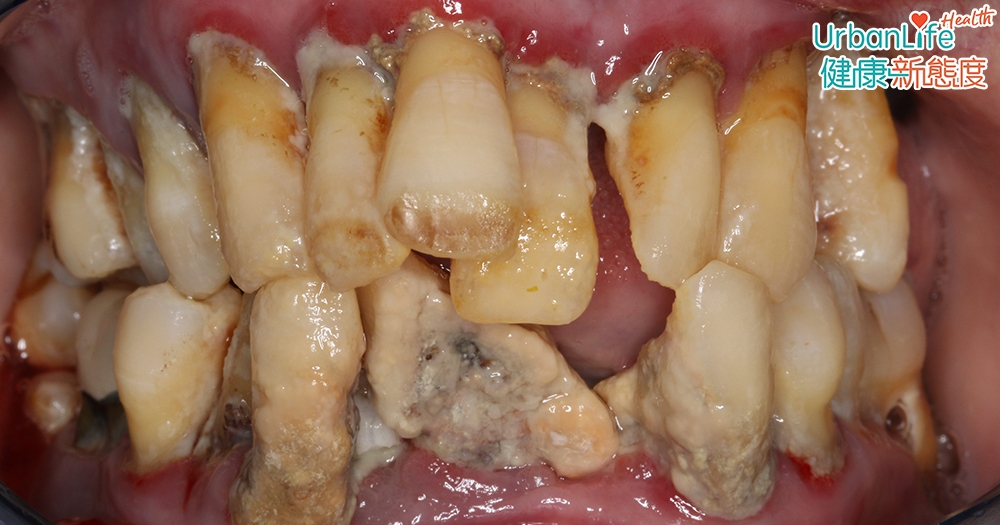

馮醫生分享一個嚴重牙周病案例。一名46歲患有嚴重牙周病的女士,因覺得牙齒很難看,同時也感到口腔味道很重,所以過往10年都很少外出。

求診時,其大部分的牙齒都已佈滿牙石,甚至失去部份牙齒。不過她卻表示,牙齒完全沒有痛楚的感覺,只是有些日子會在早上起床時掉牙,又或在進食時出現牙齒鬆動,繼而脫落的情況。

Photo from 港大牙醫學院